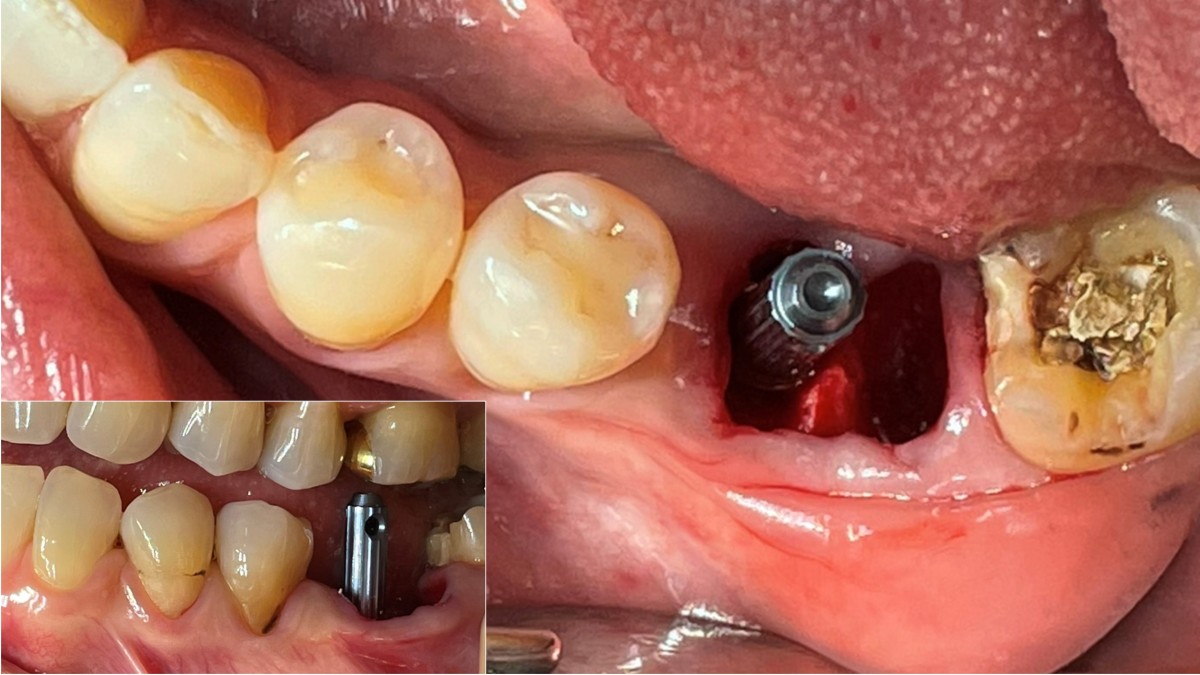

Immediate placement of an implant (Arum Dnetistry NB1, 5*8.5)

Immediate placement of an implant

A 51-year-old patient complained of an

old-crowned molar. The lower left molar had a gold crown, and the margin showed discoloration indicative of inner caries. Also, it had furcation-involved periodontitis

with an apical lesion.

Extraction and immediate placement of an implant.

▲Arum Dentistry NB1 fixture (5*8.5mm)